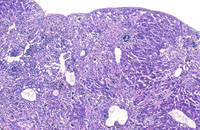

Extensive hepatic necrosis and inflammation in an athymic nude mouse with chronic mouse hepatitis virus (MHV) infection.

Mouse hepatitis virus infection in a SCID mouse. There is extensive hepatic necrosis.